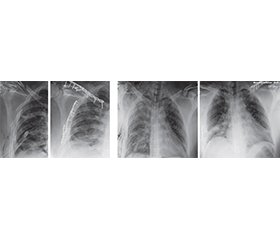

Актуальність. Серед домінуючих пошкоджень на увагу заслуговують поєднані пошкодження грудної клітки та ключиці. Травми грудної клітки є одним з основних чинників летальності у постраждалих як при ізольованих, так і при поєднаних пошкодженнях. У пацієнтів із множинними травмами, які отримали тупу травму грудної клітки, найбільш поширеними пошкодженнями є переломи ребер (86 %), переломи ключиці (19 %) або комбінація цих ушкоджень (19 %). Доведено, що переломи ключиці й ребер є маркерами тяжкості травми грудної клітки. Поєднані переломи ключиці та множинні переломи, особливо верхніх ребер, можуть призвести до тяжких деформацій грудної клітки й порушення функції у плечовому суглобі. Мета: поліпшити результати лікування пацієнтів із поєднаними пошкодженнями ключиці та грудної клітки шляхом впровадження сучасних патогенетично обґрунтованих хірургічних технологій. Матеріали та методи. Клінічне дослідження базується на обстеженні й лікуванні 47 пацієнтів із поєднаними переломами ключиці та ребер за період 2015–2024 рр. Середній вік пацієнтів становив 41,5 ± 11,9 року. Пацієнти були розподілені на дві групи: основна — 23 пацієнти, порівняльна — 24 пацієнти. Результати. Серед 47 пацієнтів із поєднаними переломами ключиці й ребер превалювали постраждалі чоловічої статі — 43 (91,5 %); відповідно, кількість травмованих жіночої статі становила 4 (8,5 %). Серед чинників травмогенезу превалюють дорожньо-транспортні пригоди: до 53,2 % випадків серед пацієнтів чоловічої статі та до 6,4 % — жіночої. Пацієнти основної групи, до яких застосовувався оперативний метод лікування (металоостеосинтез), мали статистично доведені кращі показники щодо виникнення респіраторного дистрес-синдрому (26,1 проти 54,2 % у групі консервативного лікування), післятравматичної пневмонії (33,3 проти 61,5 %), меншу потребу у штучній вентиляції легень (10,6 ± 8,4 проти 16,7 ± 7,9 доби) та коротший термін перебування у відділенні інтенсивної терапії (14,6 ± 10,6 проти 23,6 ± 10,2 доби). Висновки. 1. Сучасна концепція лікування пацієнтів із поєднаними пошкодженнями ключиці та ребер характеризується протилежними поглядами щодо вибору методу лікування й обґрунтування показань до їх застосування. 2. Пацієнти основної групи, до яких застосовано оперативний метод лікування (металоостеосинтез), мали статистично доведені ліпші показники щодо виникнення респіраторного дистрес-синдрому, післятравматичної пневмонії, меншу потребу у штучній вентиляції легень і коротший термін перебування у відділенні інтенсивної терапії.

Background. Among the dominant injuries, combined trauma to the chest and clavicle deserve attention. Chest injuries are one of the main factors of mortality in victims, both in isolated and combined injuries. In patients with multiple injuries who sustained blunt chest trauma, the most common lesions are rib fractures (86 %), clavicle fractures (19 %), or a combination of these injuries (19 %). It has been proven that clavicle and rib fractures are markers of the severity of chest trauma. Combined clavicle fractures and multiple fractures, especially of the upper ribs, can lead to severe chest deformities and dysfunction in the shoulder joint. The purpose was to improve the treatment outcomes of patients with combined injuries of the clavicle and chest by implementing modern pathogenetically based surgical technologies. Materials and methods. The clinical study is based on the examination and treatment of 47 patients with combined fractures of the clavicle and ribs from 2015 to 2024. Their average age was 41.5 ± 11.9 years. The patients were divided into two groups: the main one included 23 people and the comparative group consisted of 24 patients. Results. Among 47 patients with combined fractures of the clavicle and ribs, male victims prevailed — 43 (91.5 %), the rest 4 (8.5 %) people were females. Among the factors of traumatogenesis, road traffic accidents prevail: up to 53.2 % of cases among male patients, and up to 6.4 % of cases among females. Patients in the main group who underwent surgical treatment (metal osteosynthesis) had statistically proven better rates of respiratory distress syndrome (26.1 vs. 54.2 % in the conservative treatment group), post-traumatic pneumonia (33.3 vs. 61.5 %), less need for mechanical ventilation (10.6 ± 8.4 vs. 16.7 ± 7.9 days), and shorter length of stay in the intensive care unit (14.6 ± 10.6 vs. 23.6 ± 10.2 days). Conclusions. 1. The modern concept of treatment of patients with combined injuries of the clavicle and ribs is characterized by opposing views on the choice of therapeutic method and justification of indications for its use. 2. Patients in the main group who underwent surgical treatment (metal osteosynthesis) had statistically proven better indicators regarding the occurrence of respiratory distress syndrome, post-traumatic pneumonia, a lower need for mechanical ventilation, and a shorter stay in the intensive care unit.